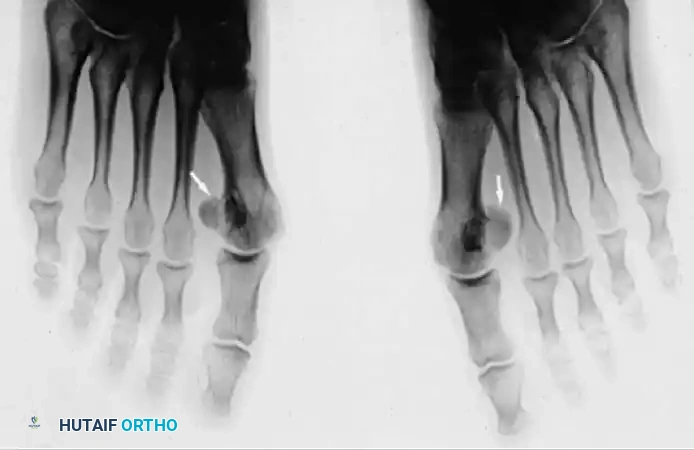

Fig. 78-95 A, Standing anteroposterior view of both feet on the same cassette allows comparison of the sesamoids. This is especially helpful if a fracture is suspected but a bipartite sesamoid is present. Accessory sesamoids (arrows) are a normal, although uncommon, finding. B, Oblique view profiles the fibular sesamoid. Note the cystic fibular sesamoid on the right foot. This probably represents an old fracture through the syndesmotic union of a bipartite sesamoid.